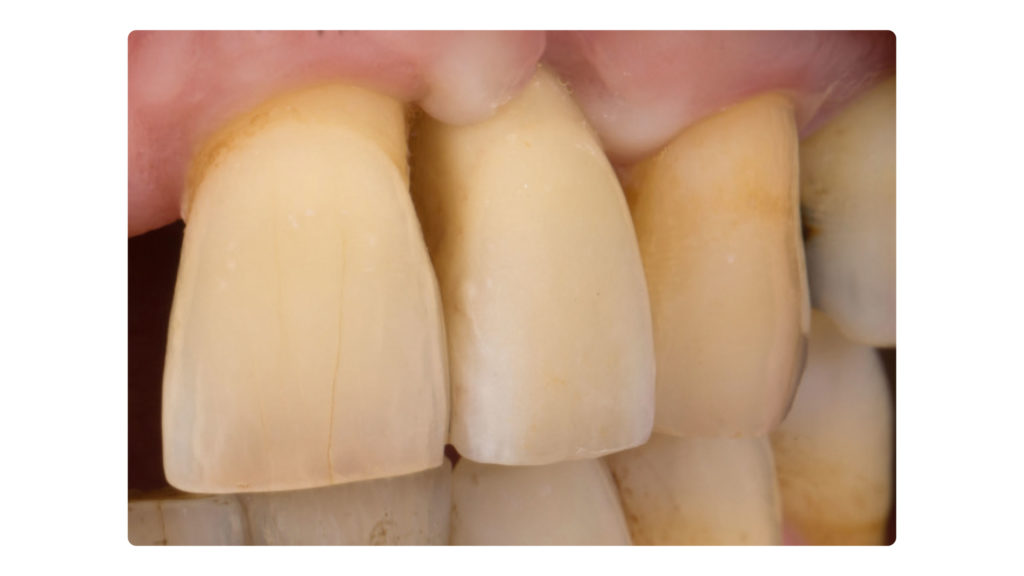

Am Tag des Einsetztermins wurden abschließend nochmals DSLR-Aufnahmen angefertigt und ausgewertet. In den Abbildung 40a und b ist die Situation mit Kreuzpolarisation festgehalte. Dadurch, dass diese Art von Fotografie störende Reflexionen an der Zahnoberfläche eliminiert, kann die Grundzahnfarbwirkung besser bewertet werden. Das Foto mit erhöhtem Kontrast verdeutlicht die internen Details und lässt einen guten Vergleich der transparenten Schmelzanteile zu (Abb. 41). Den Abschluss bildete das normale Foto der Situation mit definitiv eingegliederter Implantatkrone in regio 22. Es zeigte sich, dass die Integration sehr gut gelungen war, aber auch, wie schwierig es ist, eine nicht sichtbare Krone zu kreieren – auch wenn sie noch so klein und unscheinbar zu sein scheint (Abb. 42). Leider zeigte sich am Tag des Einsetzens anhand der Konkremente an den Zahnhälsen, dass die Zahnpflege des Patienten noch verbessert werden kann.